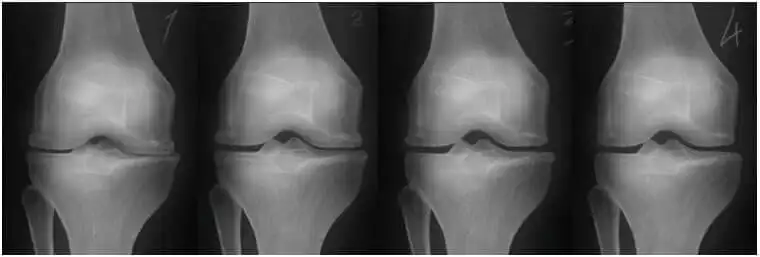

A térd ropogása nem az életkor jele – hanem segítségkérés az ízületektől

• Ropogás a térdben

Az ízületi fájdalom nem csak kellemetlen. Ha nem kezelik időben, teljesen elveheti a mozgás örömét és elszigetelheti az embert a szeretteitől.

Fontos megérteni: az ízület egy mechanizmus. Ha nincs kenőanyag, akkor tönkremegy. A Hondrofrost azért érdekes, mert összetétele segít a szervezetnek fenntartani a természetes regenerációs folyamatokat. Gyakran ajánljuk hatékony házi gyógymódként.